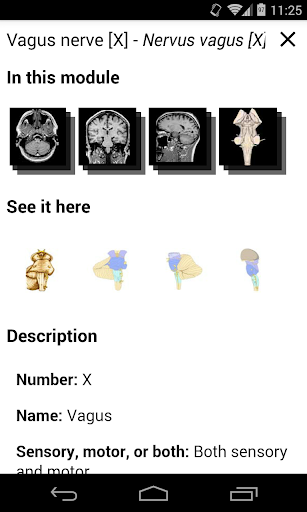

* تحسين عرض التفاصيل للأجزاء التشريحية لتسهيل التعرف عليها في صور الوحدات الحالية والوحدات الأخرى.

- يتم الآن عرض المصطلحات المتعلقة بالهيكل التشريحي في عرض التفاصيل - تمت إضافة